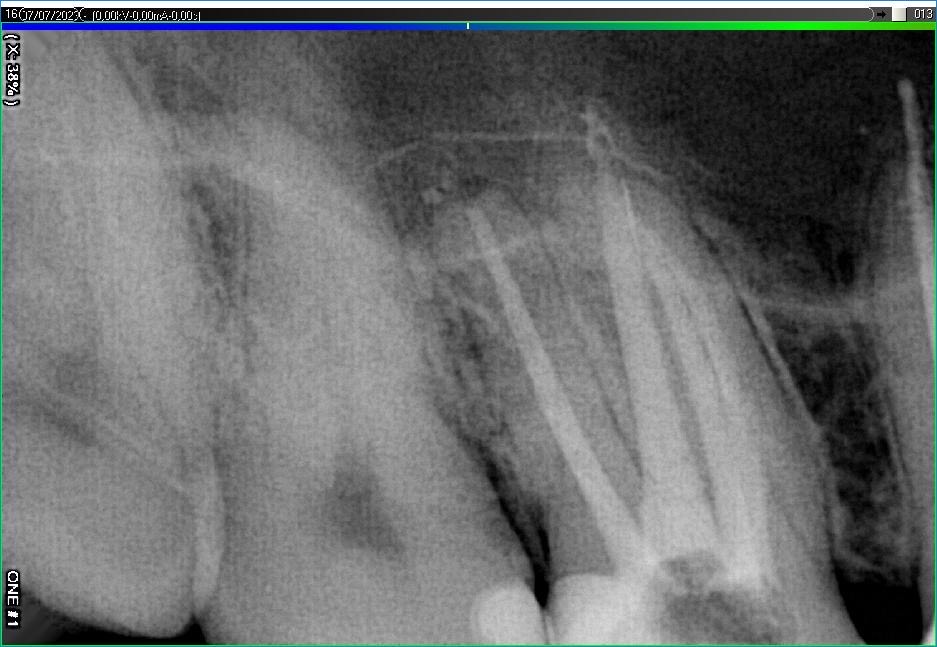

Вилучення інструменту з каналів зуба